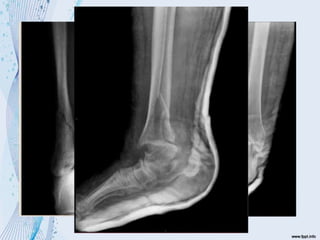

 Mecanismo de producción

Supinación – Aducción

Supinación – rotación externa

Estadio 1

- Ruptura del ligamento peroneotibial anterior

- Avulsión de su inserción

Estadio 2

- Fx espiroidal del maléolo externo

- Ruptura del ligamento peroneotibial post

Estadio 3

- Fx del maléolo tibial